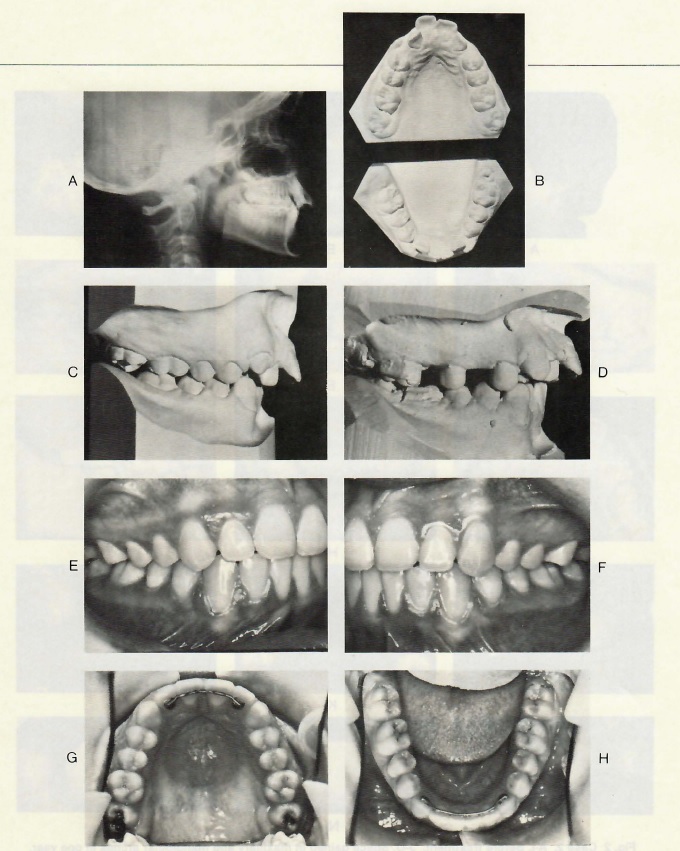

Fig. 1 Case 1. A-C. Before treatment. D. After molar distal movement. E-H. After treatment.